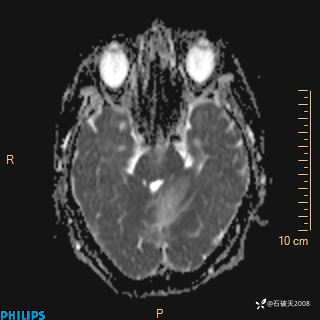

DWI